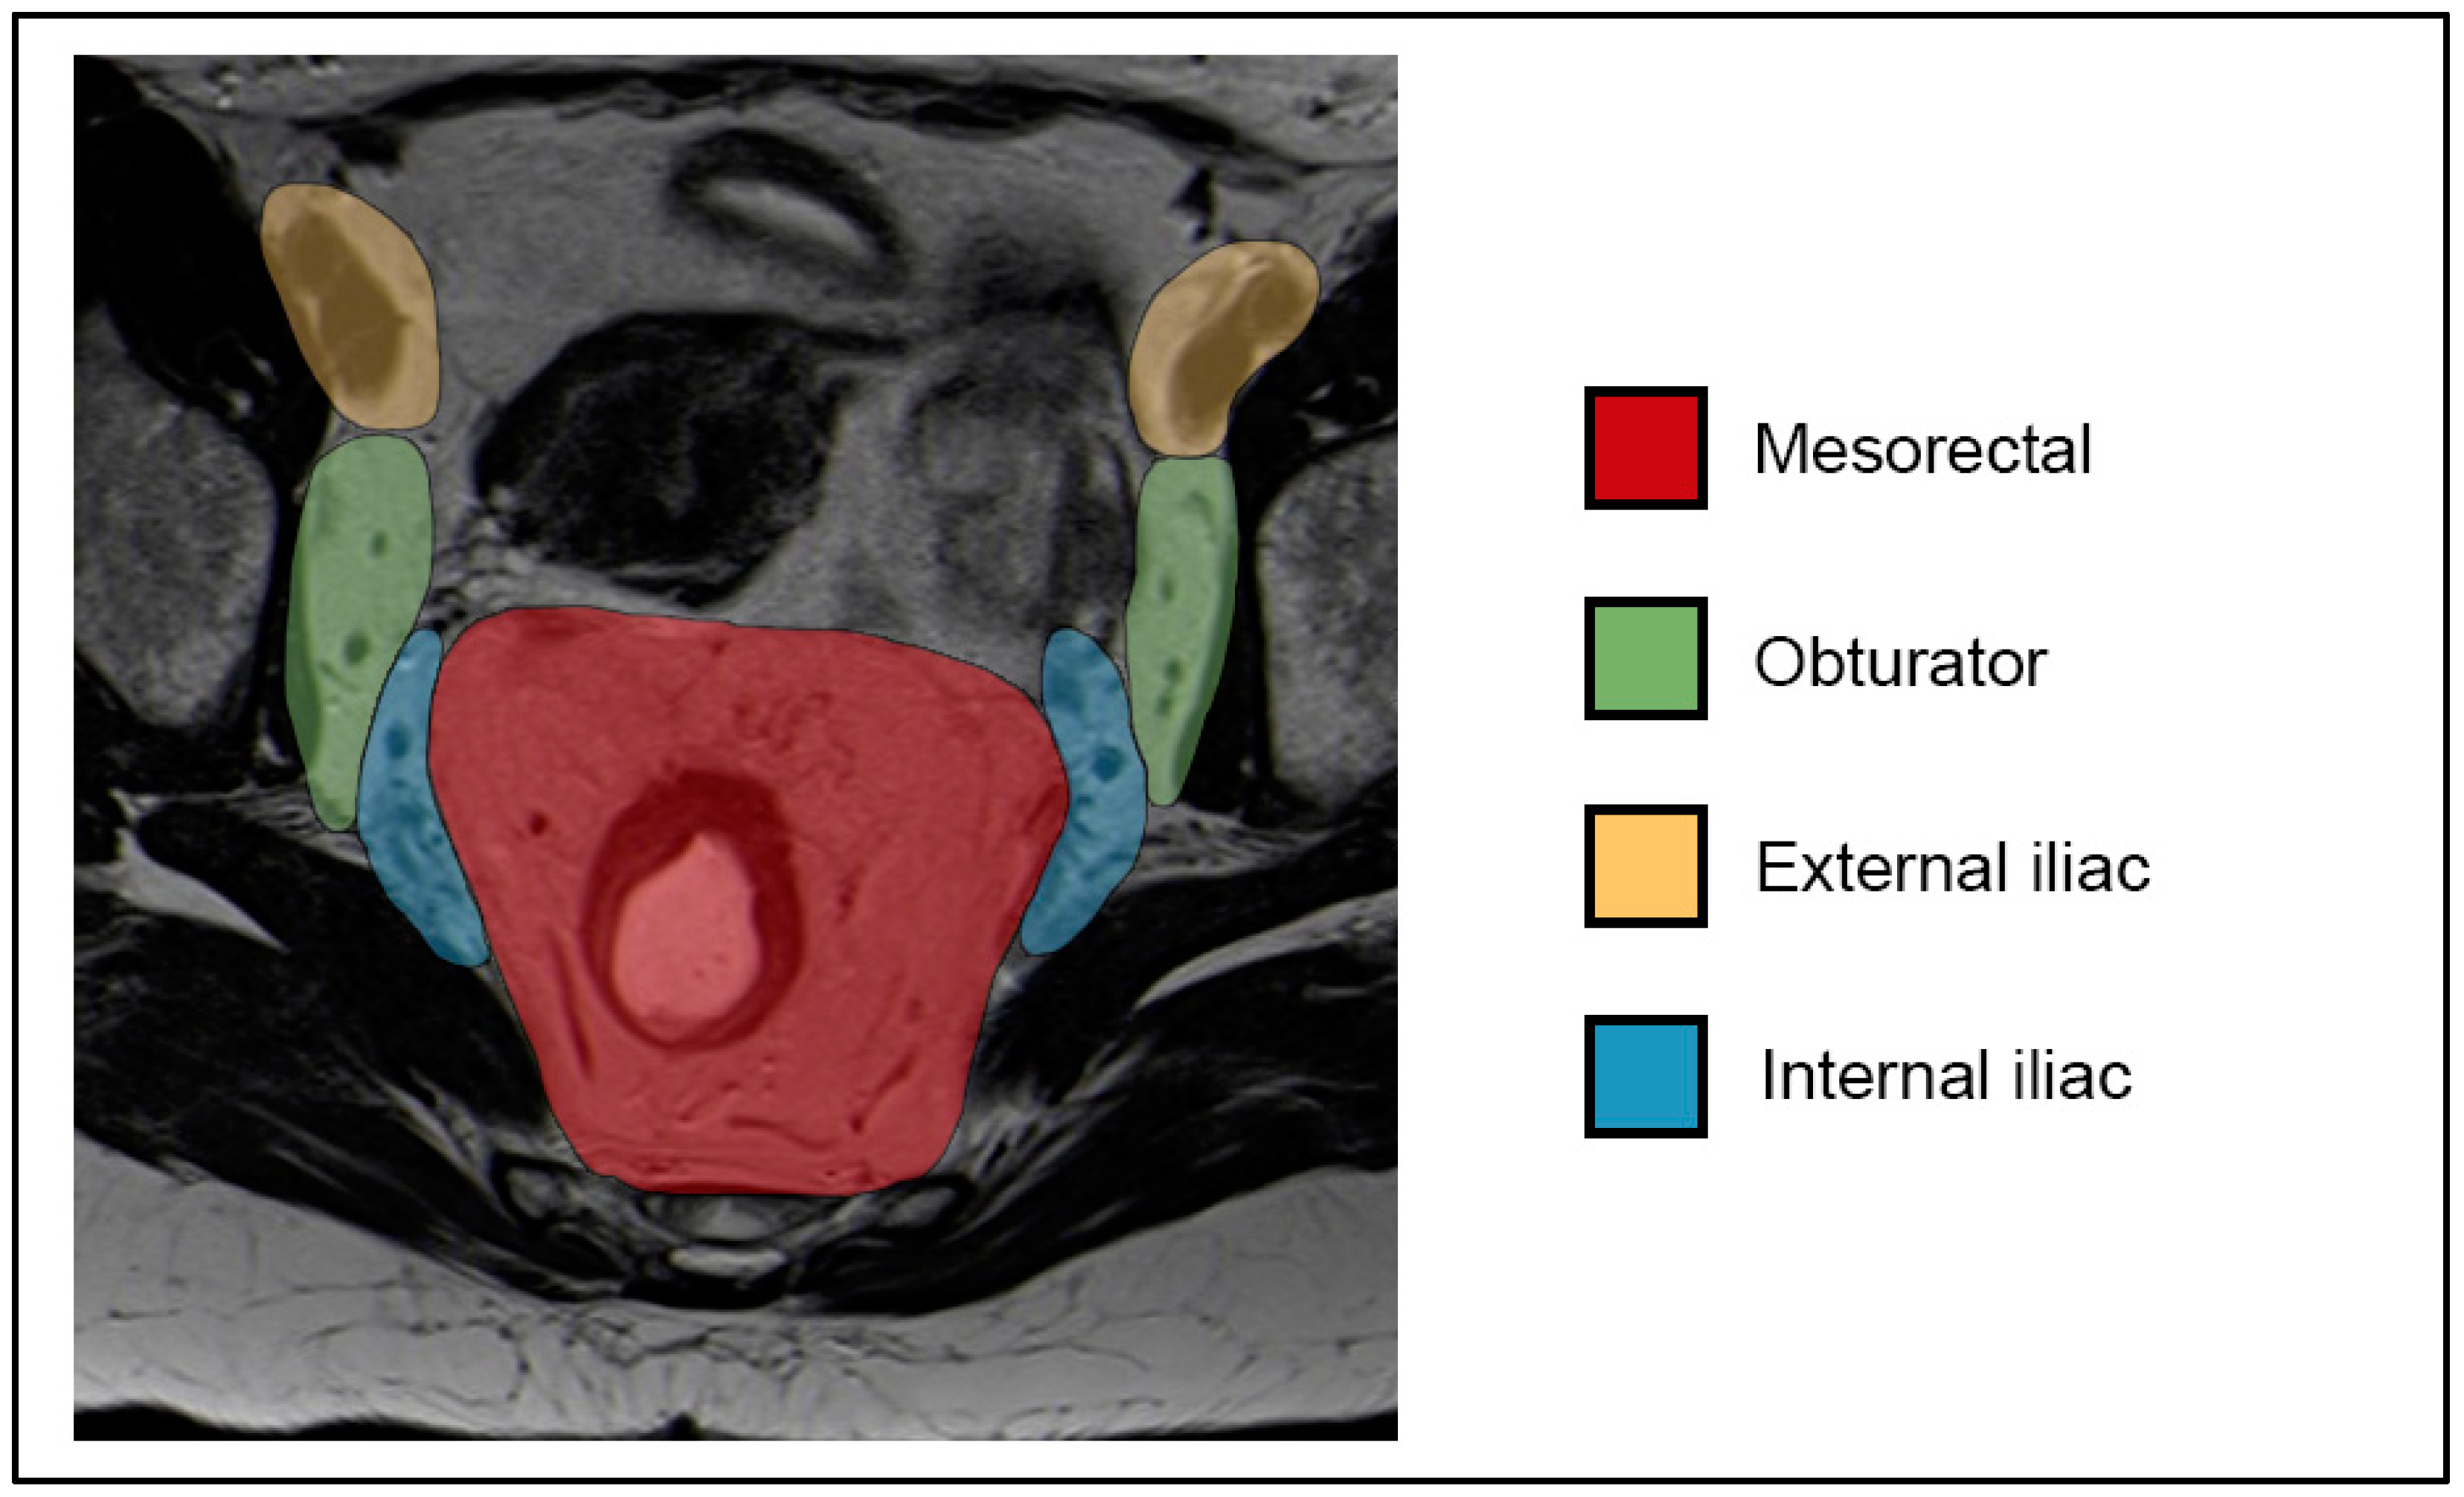

7.2. N-Staging

- Inguinal, mesorectal, internal iliac/obturator (N1a);

- External iliac (N1b);

- Both N1a and N1b (N1c);

- Common iliac, para-aortic (M1).